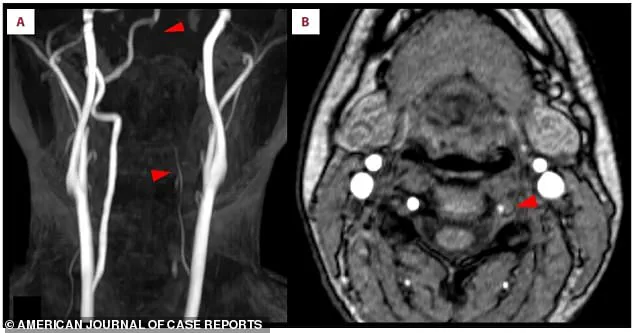

Panel A of the scan revealed bright white spots—an ominous sign of oxygen deprivation in the brain’s right occipital lobe, the region responsible for processing visual information.

Panel B provided even more damning evidence: a missing section of the right posterior cerebral artery, the very vessel that had been blocked, leaving her brain starved of blood.

The lower arrows in the same scan pointed to a troubling detail: the left vertebral artery in her neck appeared faint or broken, a critical artery that normally delivers blood to the brainstem and cerebellum.

The left vertebral artery’s diminished appearance in Scan A was a red flag.

Scan B, however, offered a definitive diagnosis: a crescent-shaped blood clot had formed inside the wall of the artery itself.